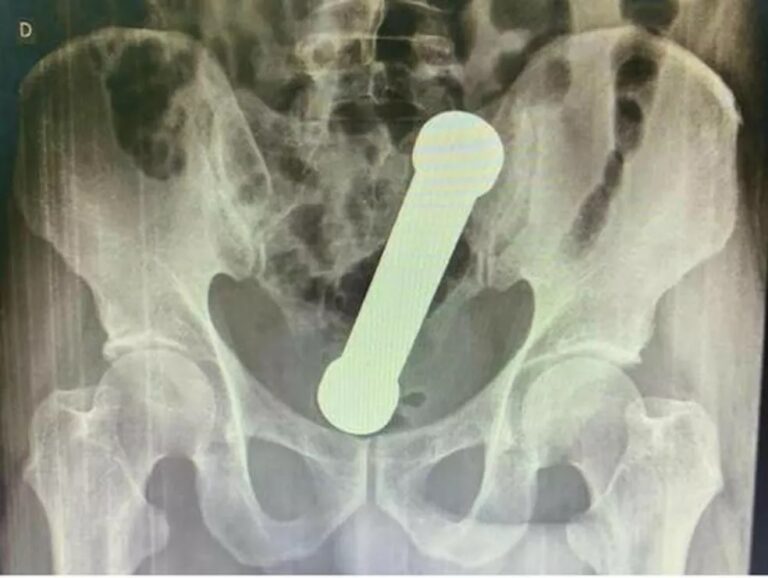

A partir do resultado do exame de radiografia, a equipe médica identificou um halter, utilizado em exercícios físicos, próximo ao reto do paciente. O homem então foi encaminhado ao centro cirúrgico e o objeto foi retirado de forma manual (veja foto mais abaixo).

O halter retirado do homem era metálico, com cerca de 20 centímetros e 2 quilos. Segundo o estudo, a taxa de sucesso para extrações como a relatada no estudo, que são raras, é de 60% a 75%.

Halter foi retirado manualmente do corpo do homem. — Foto: Reprodução/International Journal of Surgery Case Reports.